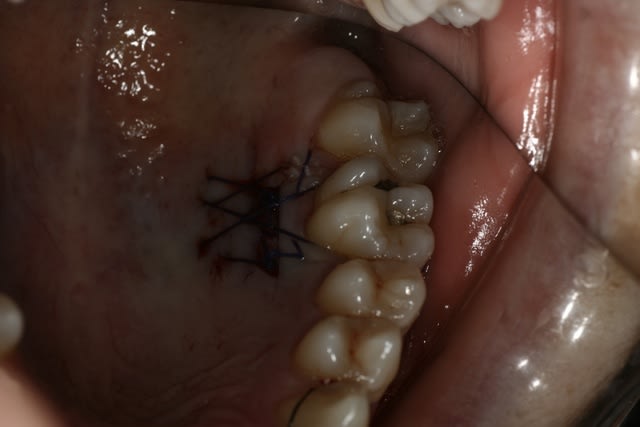

Voilà le résultat à J 0.

Le reste seulement si ça cicatrise bien.

bravo steph ... c'est propre et bien fait ......il semble que tu ais conservé un peu d'épithélium......pourquoi ?

personnellement une petite critique ......j'évite les noeuds en vestibulaire pour limiter le quantité de plaque et faciliter le nettoyage . en plus en nouant à l'intérieur le placage en lingual ou palatin se fait naturellement puisque la traction plaque le fil tout seul .....même parfois trop !

sur ce genre de cas je ne fais plus que des tunellisations et dans ce cas je ne peux garder d'épithélium .....cette technique limite enormement les sutures et je trouve donne de bons résultats.....je ne suis pas sûr que la conservation épithéliale apporte un plus ..et cela rend le travail plus difficile .....mais moi je trouves que tu maitrises tout cela parfaitement.

tu nous montre le résultat quel qu'il soit steph .. moi je suis sur que cela ira .....